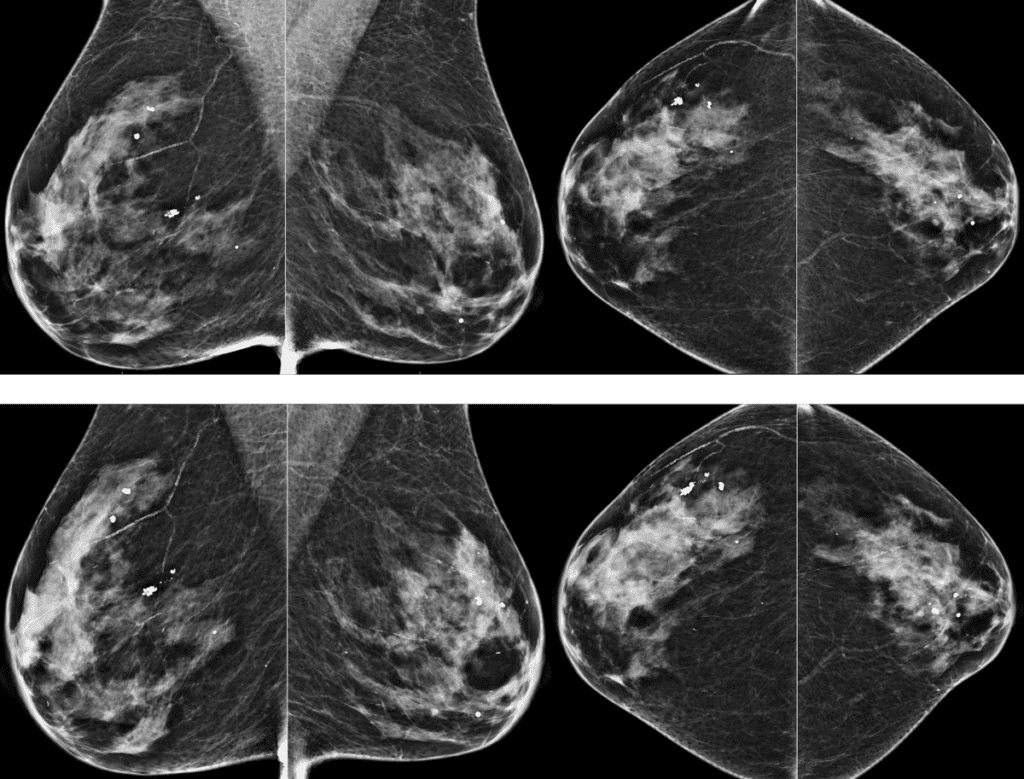

Top: Screening 2021, Bottom: Screening 2024

False Negative in Dense Breast

Post-biopsy reflector. Right breast, 7:00.